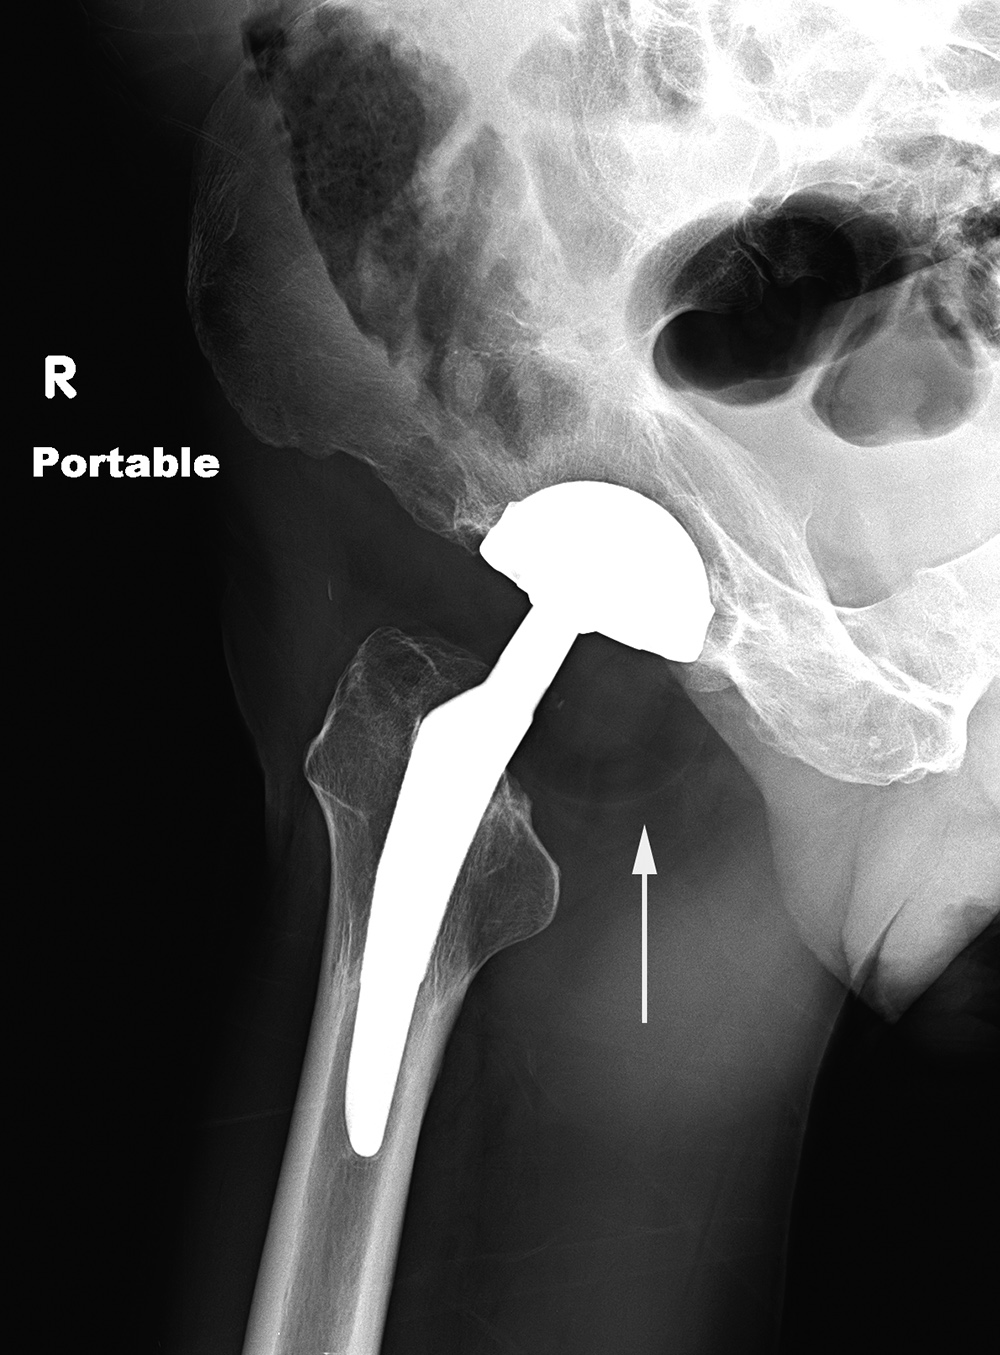

| Right hip dislocation with displaced polyethylene liner |

| Initial AP radiograph (left) shows a right hip dislocation. Note the polyethylene liner (arrow) is still associated with dislocated femoral head. The hip was subsequently relocated. The AP radiograph (middle) show subtle eccentric positioning of the reduced femoral head within the acetabular cup. A subtle density (arrows) represents the liner which is now disassociated from the femoral head. This is somewhat more clearly shown (arrow) on the frog leg lateral view (right). |